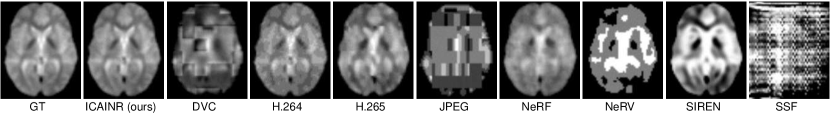

Refer to caption

Figure 1: The trace and slice comparison of an exemplar fMRI data modeled by previous INR-based methods (NeRF and NeRV) and the proposed approach.

Implicit Neural Representation (INR) is becoming increasingly widespread in various domains, such as shape representation [18, 17, 31], scene rendering [33, 62, 57, 61], and image/video representation [47, 7, 6, 5]. Due to its inherent advantages in modeling internal data correlations [46], as well as the recent development of INR-based data compression algorithms [13, 6, 49, 14, 60, 58, 59] achieving comparable or even surpassing traditional compressors, INR stands out as the most cutting-edge and promising approach in the fields of data compression and deep learning. The success of INR-based compression on videos and three-dimensional biomedical data implies the feasibility but still cannot directly support its applications on fMRI data. First, it is straightforward but difficult to directly extend existing biomedical data compression techniques [61] to 4D fMRI data. When directly employing INR to model the mapping from spatio-temporal coordinates to the signal values, the intricate dynamics [23] and heavy noise [11] might degenerate the coding accuracy and result in poor encoding accuracy in the temporal dimension, as shown in Fig. 1. Second, the INR-based compression algorithms designed for conventional videos, such as NeRV, [6], focuses on eliminating redundancies in adjacent video frames, and is not applicable to fMRI structure. The comparison is shown in Fig. 1. In summary, one should design new compression techniques to incorporate the unique features of fMRI data, including the structure, redundancy, and imaging quality.

Visual Results.

The visual comparison of the decompressed data by various algorithms at a fixed compression ratio (similar-to\sim100×\times) is shown in Fig. 5. Note that the actual achieved compression ratio of different algorithms differs slightly, are shown in Tab. 1, because one cannot specified the final compression ratio exactly. From the results, it is evident that despite yielding relatively high PSNR and SSIM values, many algorithms failed to deliver satisfactory visual quality. For instance, JPEG and DVC suffer from block effect[26], with noticeable fragmentation between adjacent image blocks. The INR-based algorithms, like NeRF, SIREN, and NeRV, sacrificed a considerable amount of high frequency details and thus show over-smoothness. Differently, other algorithms such as H.264 and H.265 exhibited noticeable noise, and it seems that SSF almost fail to model the fMRI data.